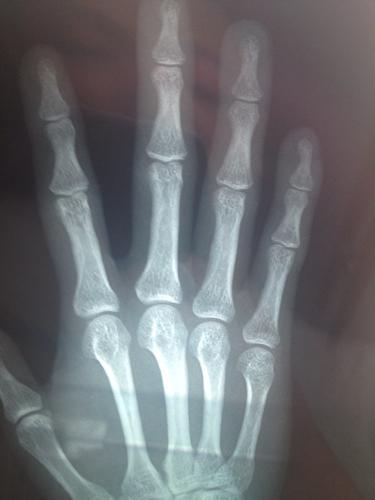

女生骨骺线什么时候闭合

身高已经有一年以上没有变化,那可能表示你的骨骺线已经开始闭合,普通的自然生长已经不能使你的骨骼继续增长。

身体变得结实:

全身肌肉,特别是小腿的肌肉,肚子,手臂等增加的比较快时,以及当体重增加的比较快的时候,像平时一样正常饮食,但发现自己重却上升的很快,这也意味着骨骺在变化。